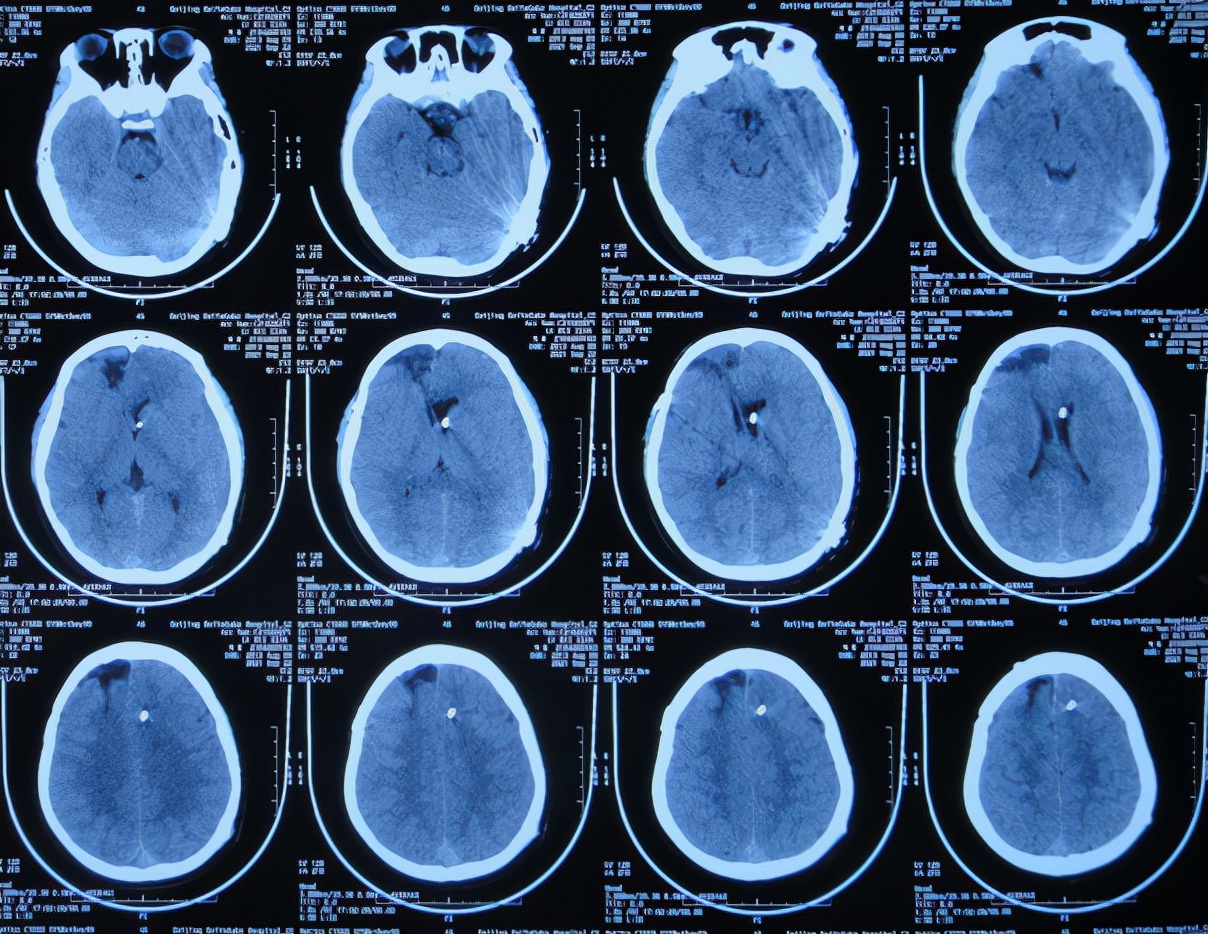

入院当天查脑CT示脑室扩张,硬膜下水肿( 图-8 )。

图-8: 2021年4月27日入院时脑CT

入院当天进行了拔除了原外院腰大池引流管+脑室外引流术( 图-9 )。

图-9: 2021年4月27日术后脑CT

脑室外引流术后9天即2021年5月6日,病情好转:头痛完全消失,睡眠时小便*禁失**变正常,脑脊液变清亮但脑脊液蛋白仍高( 图-10 );查脑CT示脑室较入院时缩小,硬膜下水肿也有减轻( 图-11 )。

图-11: 2021年5月6日脑CT

2021年7月29日(入院治疗3个月),体温连续一个月正常,脑CT示仍有少量水肿( 图-13 ),但 身体未见异常。

图-13: 2021年7月29日脑CT

2021年9月10日(入院治疗4月半),脑脊液各项指标均正常后按计划进行了脑室腹腔分流术( 图-15 )。

图-15: 2021年9月10日脑CT